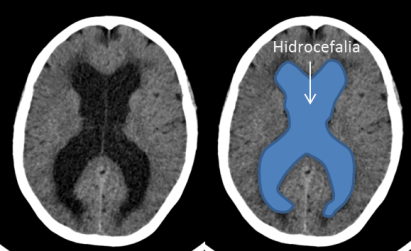

La presentación clínica de un quiste coloide del III ventrículo puede ser la misma que la de una hidrocefalia a presión normal (alteración de la marcha, incontinencia urinaria y alteración cognitiva). Los quistes coloides del III ventrículo se suelen ver en la TAC cerebral sin contraste porque en 2/3 de las ocasiones son hiperdensos pero en 1/3 de los casos como éste caso son isodensos/hipodensos y pueden pasar desapercibidos inicialmente. Además hay que tener en cuenta que cuando se introduce contraste en la TAC cerebral puede no verse tampoco. Únicamente tras la realización de la resonancia cerebral se pudo diagnosticar por su hiperintensidad en secuencias T1 (imagen 3) y su hipointensidad en secuencias en T2.

En la imagen 4 se puede intuir la presencia del quiste coloide que inicialmente había pasado desapercibido.